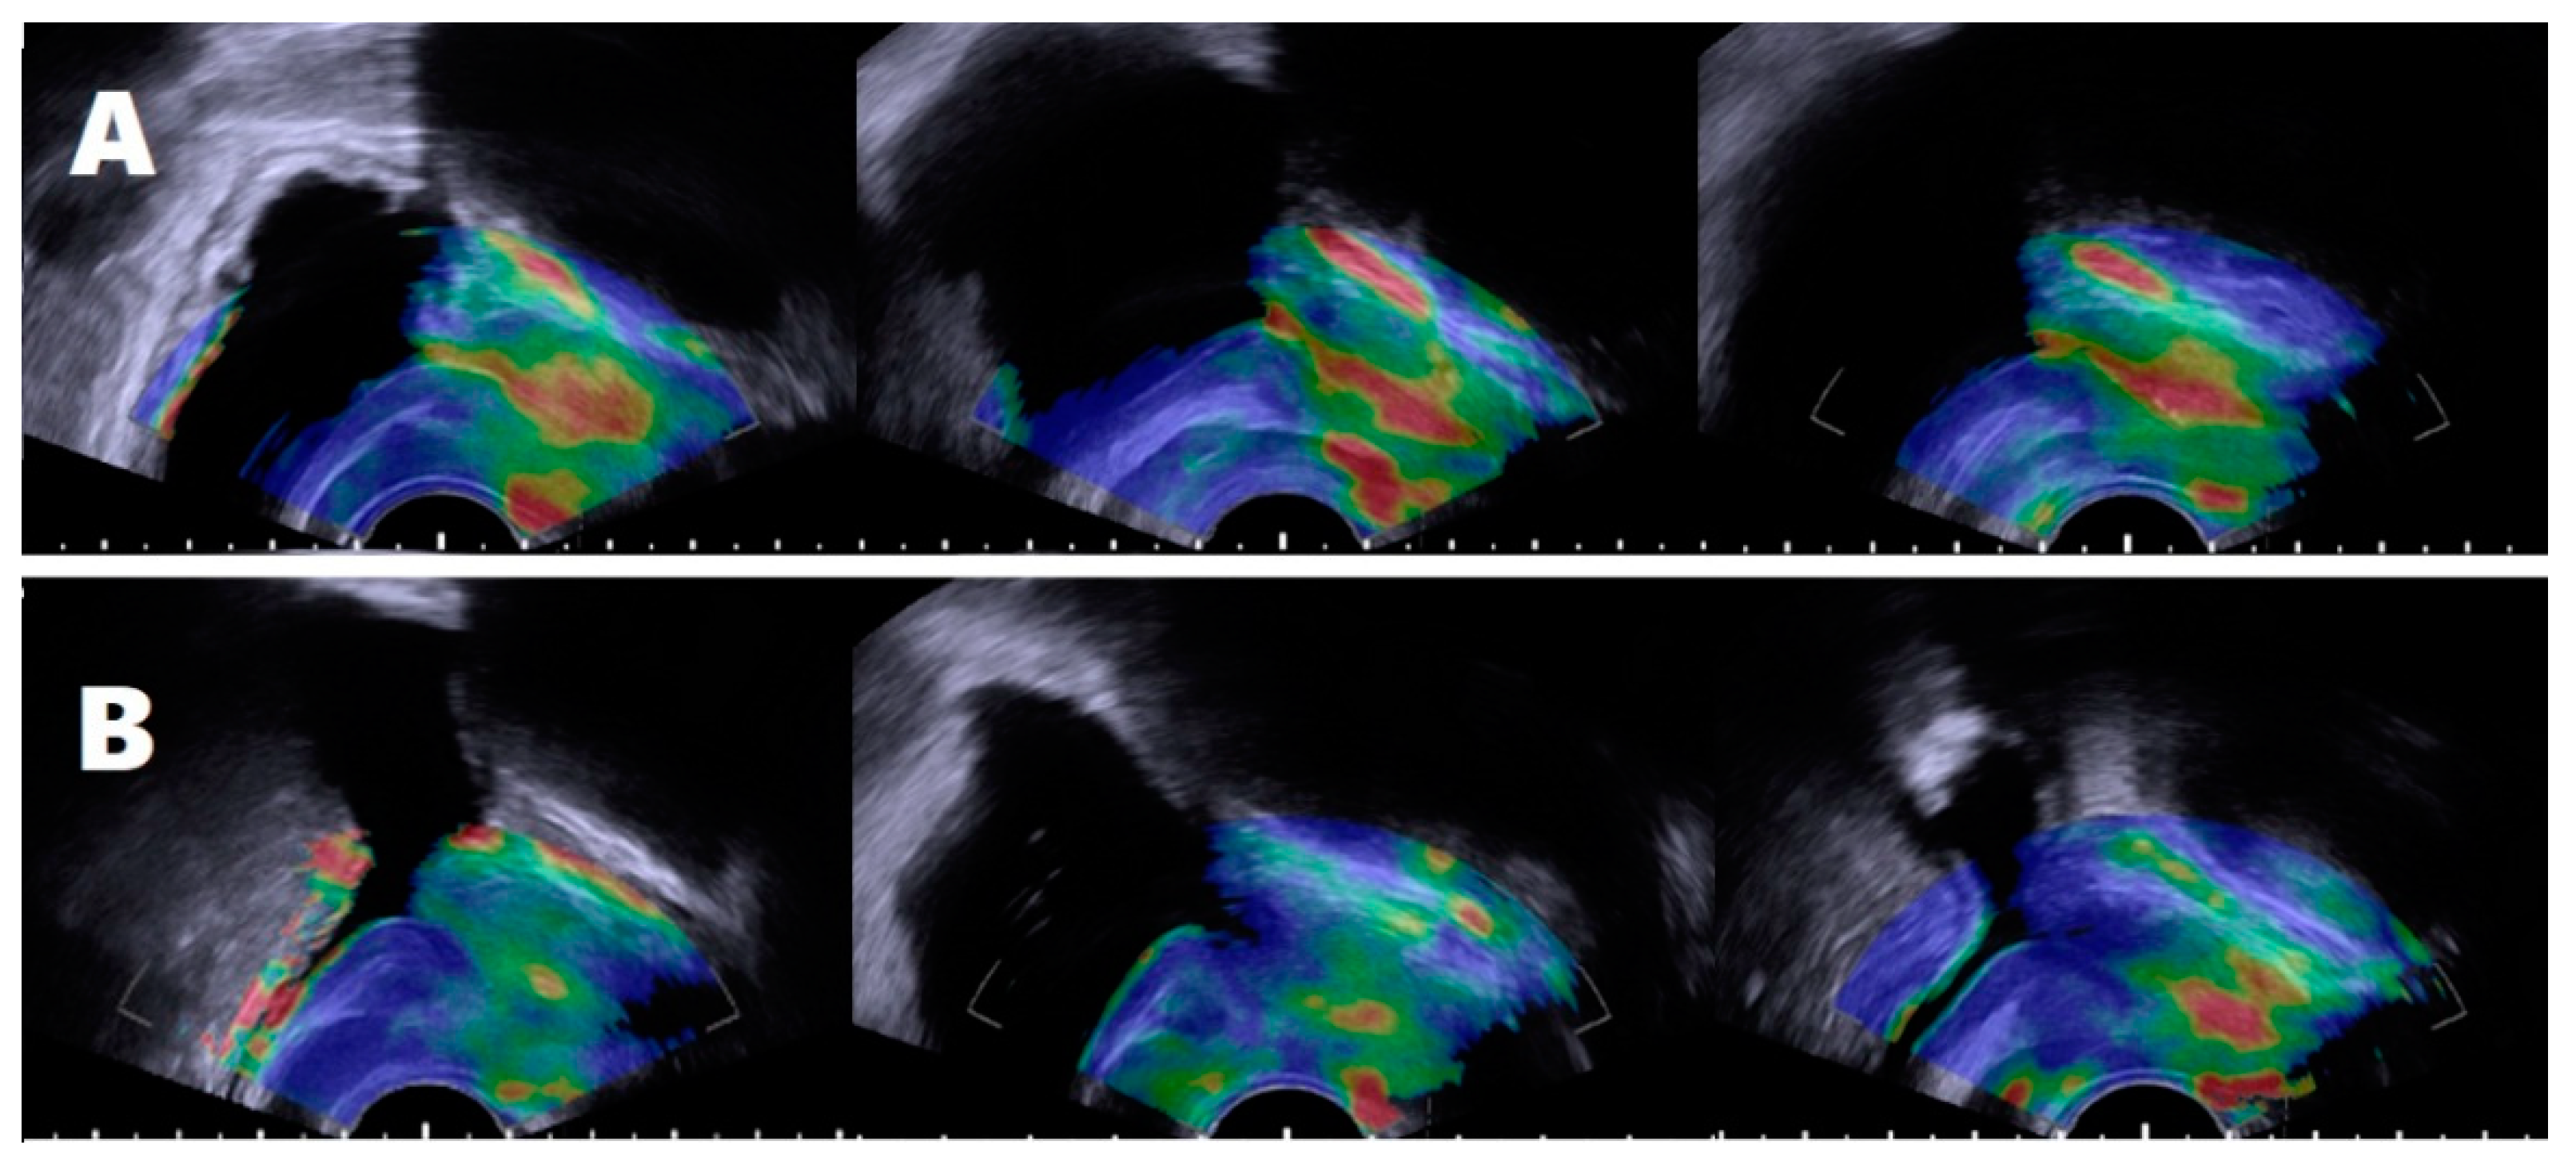

2.2. Assessment of Prostatic Anatomical Factors Using TRUS and Elastography

2.3. Defining the Subject’s Groups According to Periurethral Elastography